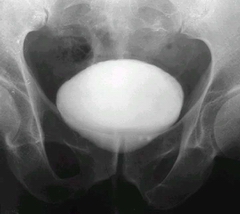

老人得了膀胱結石的癥狀?老年人年紀一大,身體素質也就會下降不少,很多疾病也就找上門了,今天要跟大家介紹的就是比較多見的膀胱結石,下面來了解下膀胱結石都有什么癥狀吧。

齊齊哈爾?現代專家說,膀胱結石的具體癥狀表現有以下幾種:

一、排尿困難:典型的膀胱結石的癥狀是患者在排尿時尿流突然中斷和陰莖頭部劇痛,這是由于結石突然嵌頓在尿道內口引起膀胱括約肌的痙攣所致。當患者變換體位而使結石移動時,又可排尿而劇痛得以緩解。出現膀胱結石的癥狀后,患者為避免排尿時發(fā)生劇烈疼痛,常呈特殊排尿體位,即站立排尿時雙膝前屈,軀干部后仰約30度,排尿時小心翼翼,如有尿線變細或中斷,再適當變動體位使結石移動后再行排尿。有的患者可有排砂石的病史。

二、疼痛:膀胱結石的癥狀中的疼痛可為下腹部和會陰區(qū)鈍痛,也可為明顯疼痛,常因活動而誘發(fā)或加劇。

三、膀胱刺激:膀胱結石合并感染時,出現膀胱刺激癥狀、血尿和膿尿。膀胱結石由于對膀胱局部的刺激、梗阻和繼發(fā)感染,可產生各種膀胱結石的癥狀。結石引起的膀胱刺激、繼發(fā)慢性炎性反應可引起膀胱鱗狀上皮癌等比較嚴重的并發(fā)癥,所以膀胱結石應早治療,必須高度重視。

四、結石刺激膀胱黏膜時,膀胱結石的癥狀可有尿頻、尿急、尿痛,排尿終末時疼痛加劇,且可伴有終末血尿。患者常改變體位如臥位以求疼痛緩解。